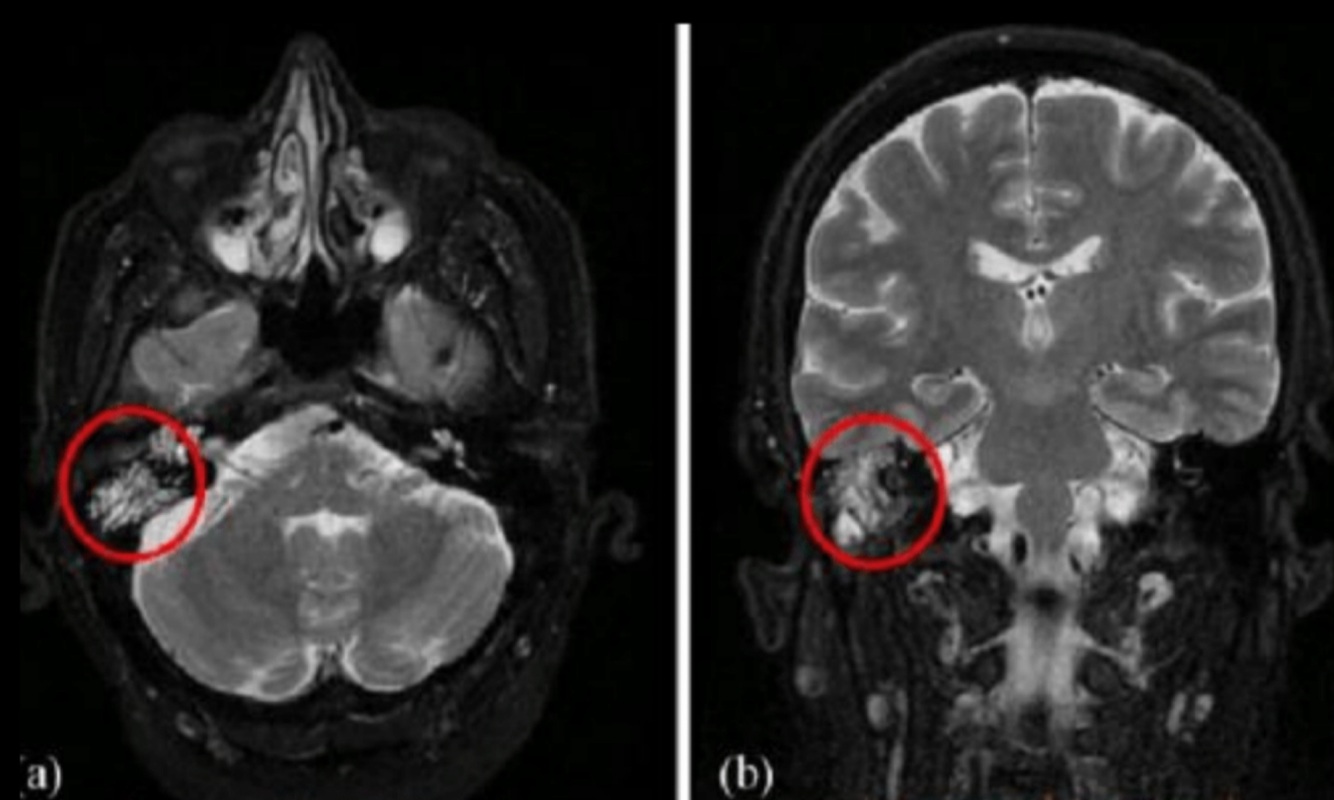

¿Para qué se usa la MRI?

Extensión intracraneal

➞Meningitis

➞Abscesos por complicación

Hallazgos de T2 en mastoiditis complicada:

• Señal aumentada

• Disminución de señal en seno sigmoideo

• Capta contraste